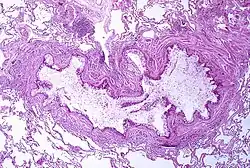

Patofizjologia

Astma jest rezultatem przewlekłego zapalenia dróg oddechowych, którego efektem jest zwiększona kurczliwość mięśni gładkich dróg oddechowych[16]. Wraz z innymi czynnikami prowadzi to do zwężenia dróg oddechowych, którego objawem jest świszczący oddech[16]. Zwężenie zazwyczaj mija niezależnie od tego, czy jest leczone, czy też nie[16]. Czasami może dochodzić do histologicznej przebudowy tkanek dróg oddechowych[16]. Najczęściej spotykane zmiany dróg oddechowych obejmują zwiększenie ilości eozynofili oraz pogrubienie blaszki siateczkowatej[15]. Po pewnym czasie mięśnie gładkie dróg oddechowych mogą zwiększyć swój rozmiar; może się także zwiększyć liczba gruczołów śluzowych[15]. Inne rodzaje uczestniczących w tym procesie komórek to limfocyty T, makrofagi oraz neutrofile[15]. Może również dochodzić do zaangażowania innych części układu immunologicznego, włączając w to m.in.: cytokiny, chemokiny, histaminę oraz leukotrieny[15].